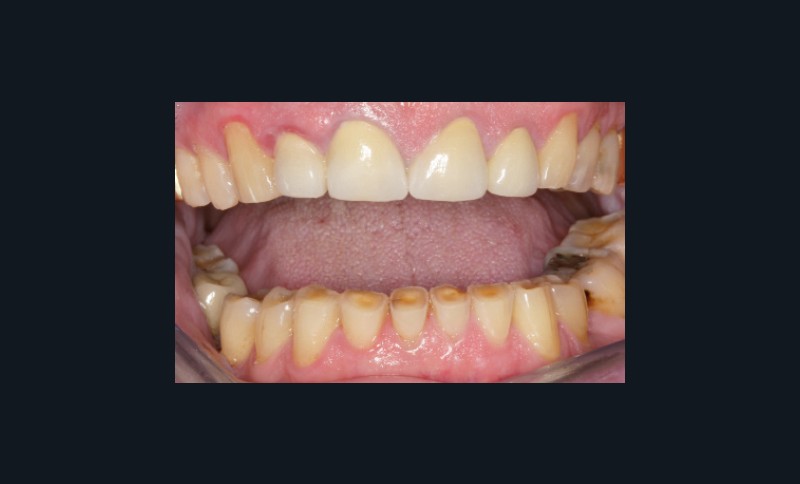

Bruxisme : net avec attrition antérieure marquée en particulier en regard des coiffes céramiques.

Occlusion : décentrage gauche, création d’une légère béance antérieure probable conséquence

de l’atteinte de l’ATM gauche.

Indication de prise en charge du bruxisme du fait de l’ATM fragile, contact avec médecin traitant à propos de l’arthrite dégénérative, pas de gouttière initiale.

Renforcement de la PECC par des collages en composite sur 13 et 23, Réévaluation sur 12 mois…